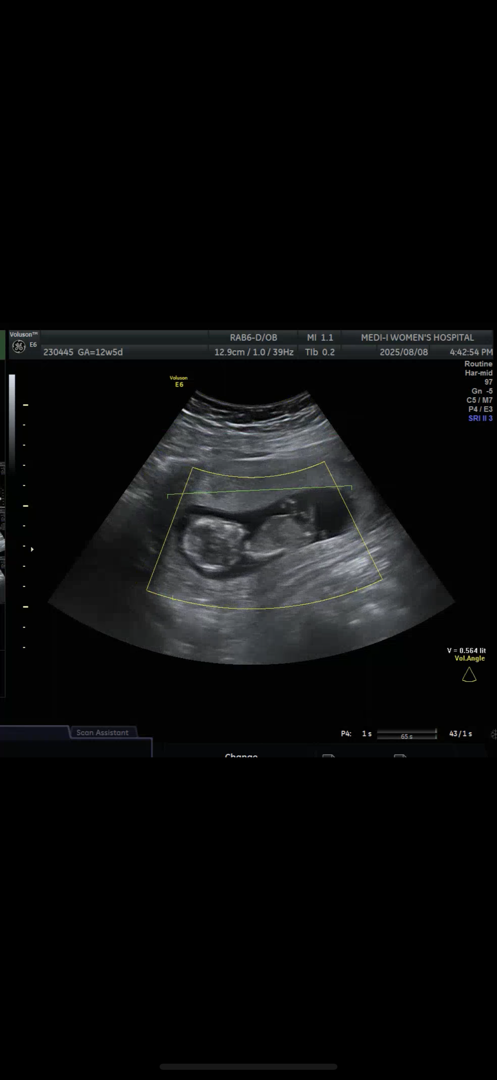

12주 5일차 각도법

안녕하세요! 오늘이 12주 5일차로 초기 정밀 초음파 받고 왔습니다 ㅎㅎ 혹시 각도법 봐주실 수 있을까요?ㅜㅜ